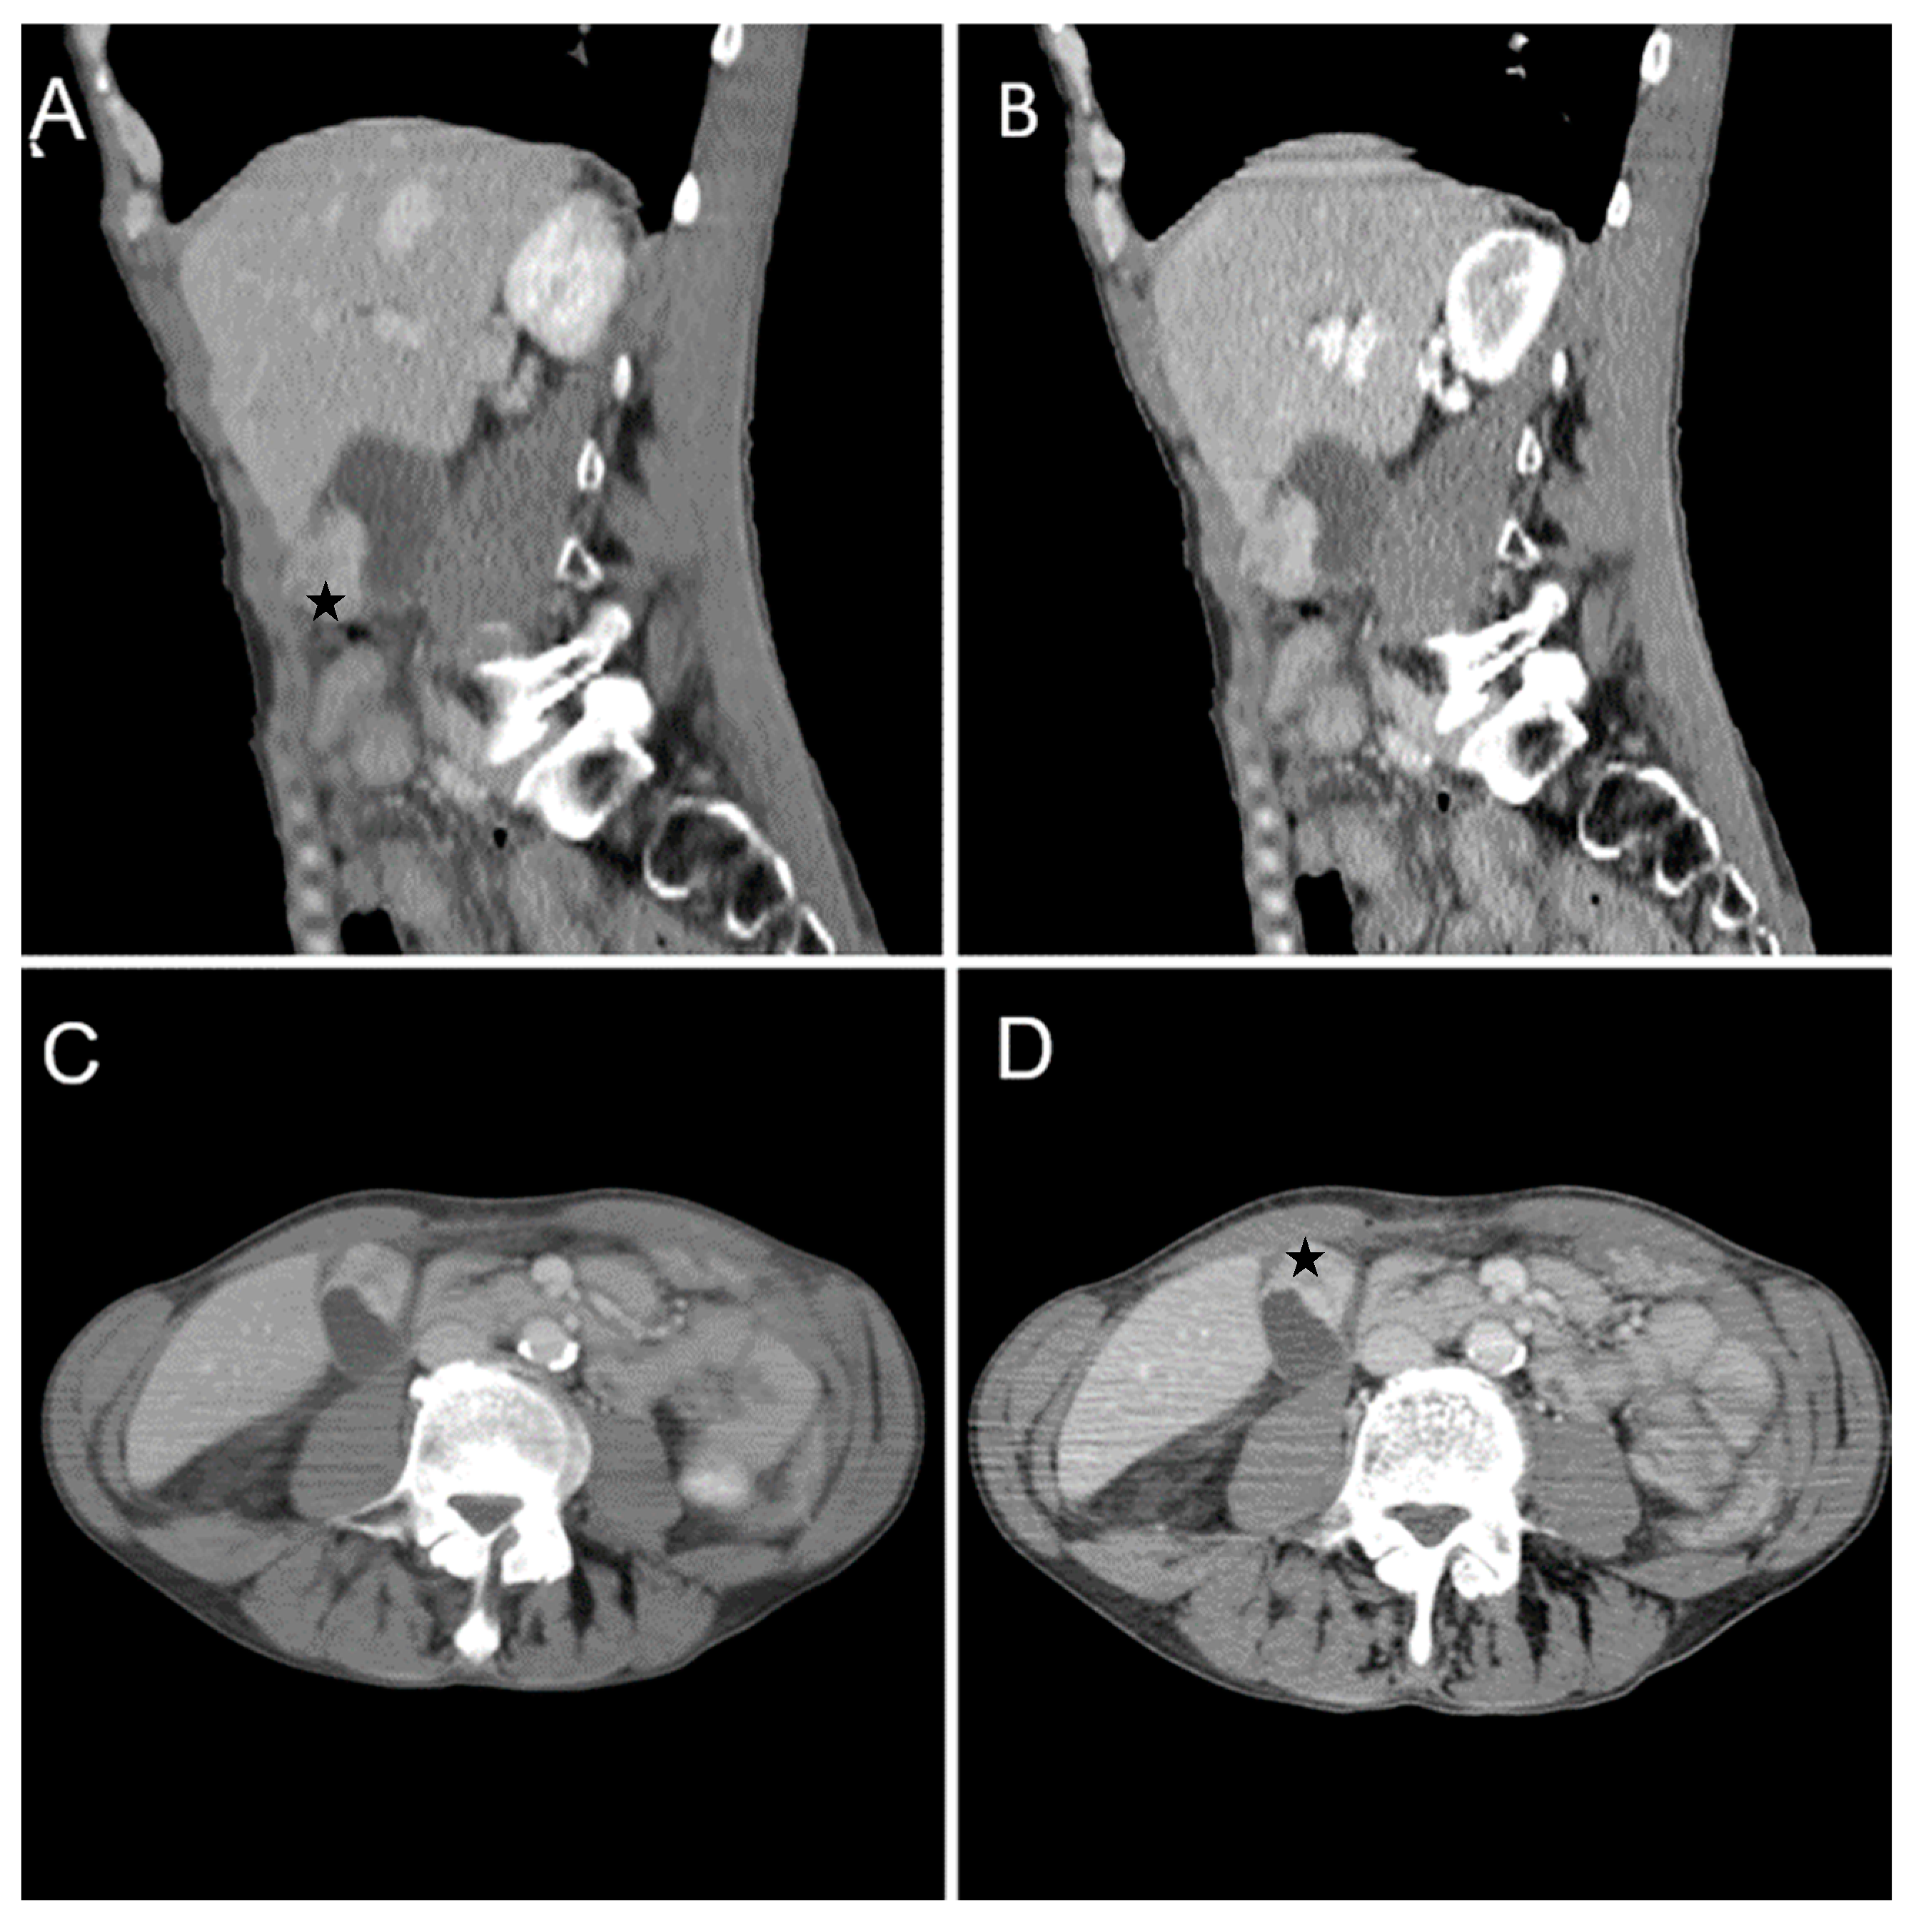

Figure 9. Multiplanar sections of contrast-enhanced CT acquisitions richly illustrating gallbladder carcinoma. (AD). A large, inhomogeneous pseudonodular mass with heterogeneous contrast enhancement, with invasion in the adjacent liver, pyloric antrum and duodenum II (white arrows). (A) Lymphatic metastases; with compressive effect on the inferior vena cava and right renal artery and vein (blue arrow).

A 67-year-old female patient with a past medical history of hypertension and autoimmune thyroiditis presented to the Emergency Department with abdominal pain accompanied by nausea and weight loss. Physical examinations revealed abdominal tenderness with a palpable mass in the right hypochondrium. Blood sample demonstrated elevated inflammatory markers, hypochromic microcytic anemia, hepatic cytolysis and increased levels of CEA (12.5 ng/mL) and CA 19-9 (51 U/mL). Contrast-enhanced emergency CT (Figure 9) showed a large mass with heterogeneous enhancement, measuring 94/57 mm, that partially replaced the gallbladder and invaded the liver (segment IVb), pyloric antrum and duodenum II. Bulky celiac and mesenteric lymphadenopathies with areas of necrosis, measuring up to 27/25 mm were present.

Abdominal MRI was performed (Figure 10).

Endoscopic ultrasound-guided fine-needle aspiration (EUS-FNA) for gallbladder tissue was performed and revealed epithelial gallbladder carcinoma. The biopsy specimens were processed for frozen sectioning. Formalin-fixed paraffin-embedded tissue sections from the gallbladder were examined histologically. The microscopic description revealed proliferation of polygonal cells, abundant clear cytoplasm, large nuclei with irregular membranes and atypical mitotic divisions.

Figure 14. We present a rare and unusual case of a 67-year-old male with a medical history of cutaneous melanoma on right thorax stage IV. CT images fully illustrated a contrast-enhancing polypoid pseudonodular mass located in the gallbladder fundus measuring 21/20 mm (white arrows). (A) Native examination: 55–60 HU. (B) Arterial phase: 95–119 HU. (C) Venous phase: 80–100 HU. (D) Delayed phase (3 min): 75–80 HU. MRI was performed (Figure 15). Melanin is usually hyperdense on unenhanced CT images and hyperintense on T1-weighted MRI; this criterion plays an essential role in the differential diagnosis between primary or secondary gallbladder lesions. The patient followed immunotherapy.